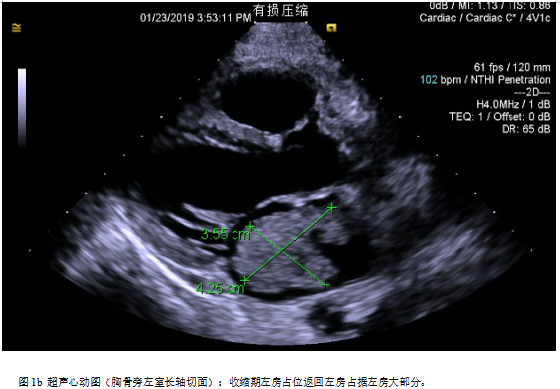

诊断:左房占位主要根据间断胸闷憋喘伴咳嗽等临床症状结合影像学主要是超声心动图评估作出诊断;根据超声心动图检查,可见左房占位蒂附着于房间隔左房面与卵圆窝相应的位置,单发,通过形态及活动度,考虑为单纯粘液瘤。

手术:目前左房粘液瘤患者手术指征粘液瘤可阻塞瓣膜开口导致心力衰竭或心跳骤停,瘤栓脱落导致脑检塞等也可以引起死亡。因此,一且确诊,立即争取手术治疗。一般心脏患者如有长期发热、心力衰竭、贫血、血沉增快等现象,须延缓手术。但对心脏粘液瘤患者需具体分析,否则可能丧失手术机会。如有高热、血沉快,全身症状为主要表现,并且考虑是由粘液瘤引起,应立即手术,摘除肿瘤能使体温下降、心率变慢、血沉恢复正常、心衰得到控制。如果感染性心内膜炎引起的高热、心力衰過,不宜急于手术,应该控制高热、心衰后手术,以免发生严重的并发症[1-2]。该患者左房占位病变巨大,且血流动力学不稳定,肿物随左心室舒张通过二尖瓣从左房脱入左室,左心室收缩又返流回左房,因粘液瘤部分阻塞二尖瓣口,随体位变化有间歇性昏厥的患者,我们选择严格限制卧床体息,应用静脉滴注多巴胺强心维持血压,同时给予利尿药减轻肺水肿,准备急症手术。